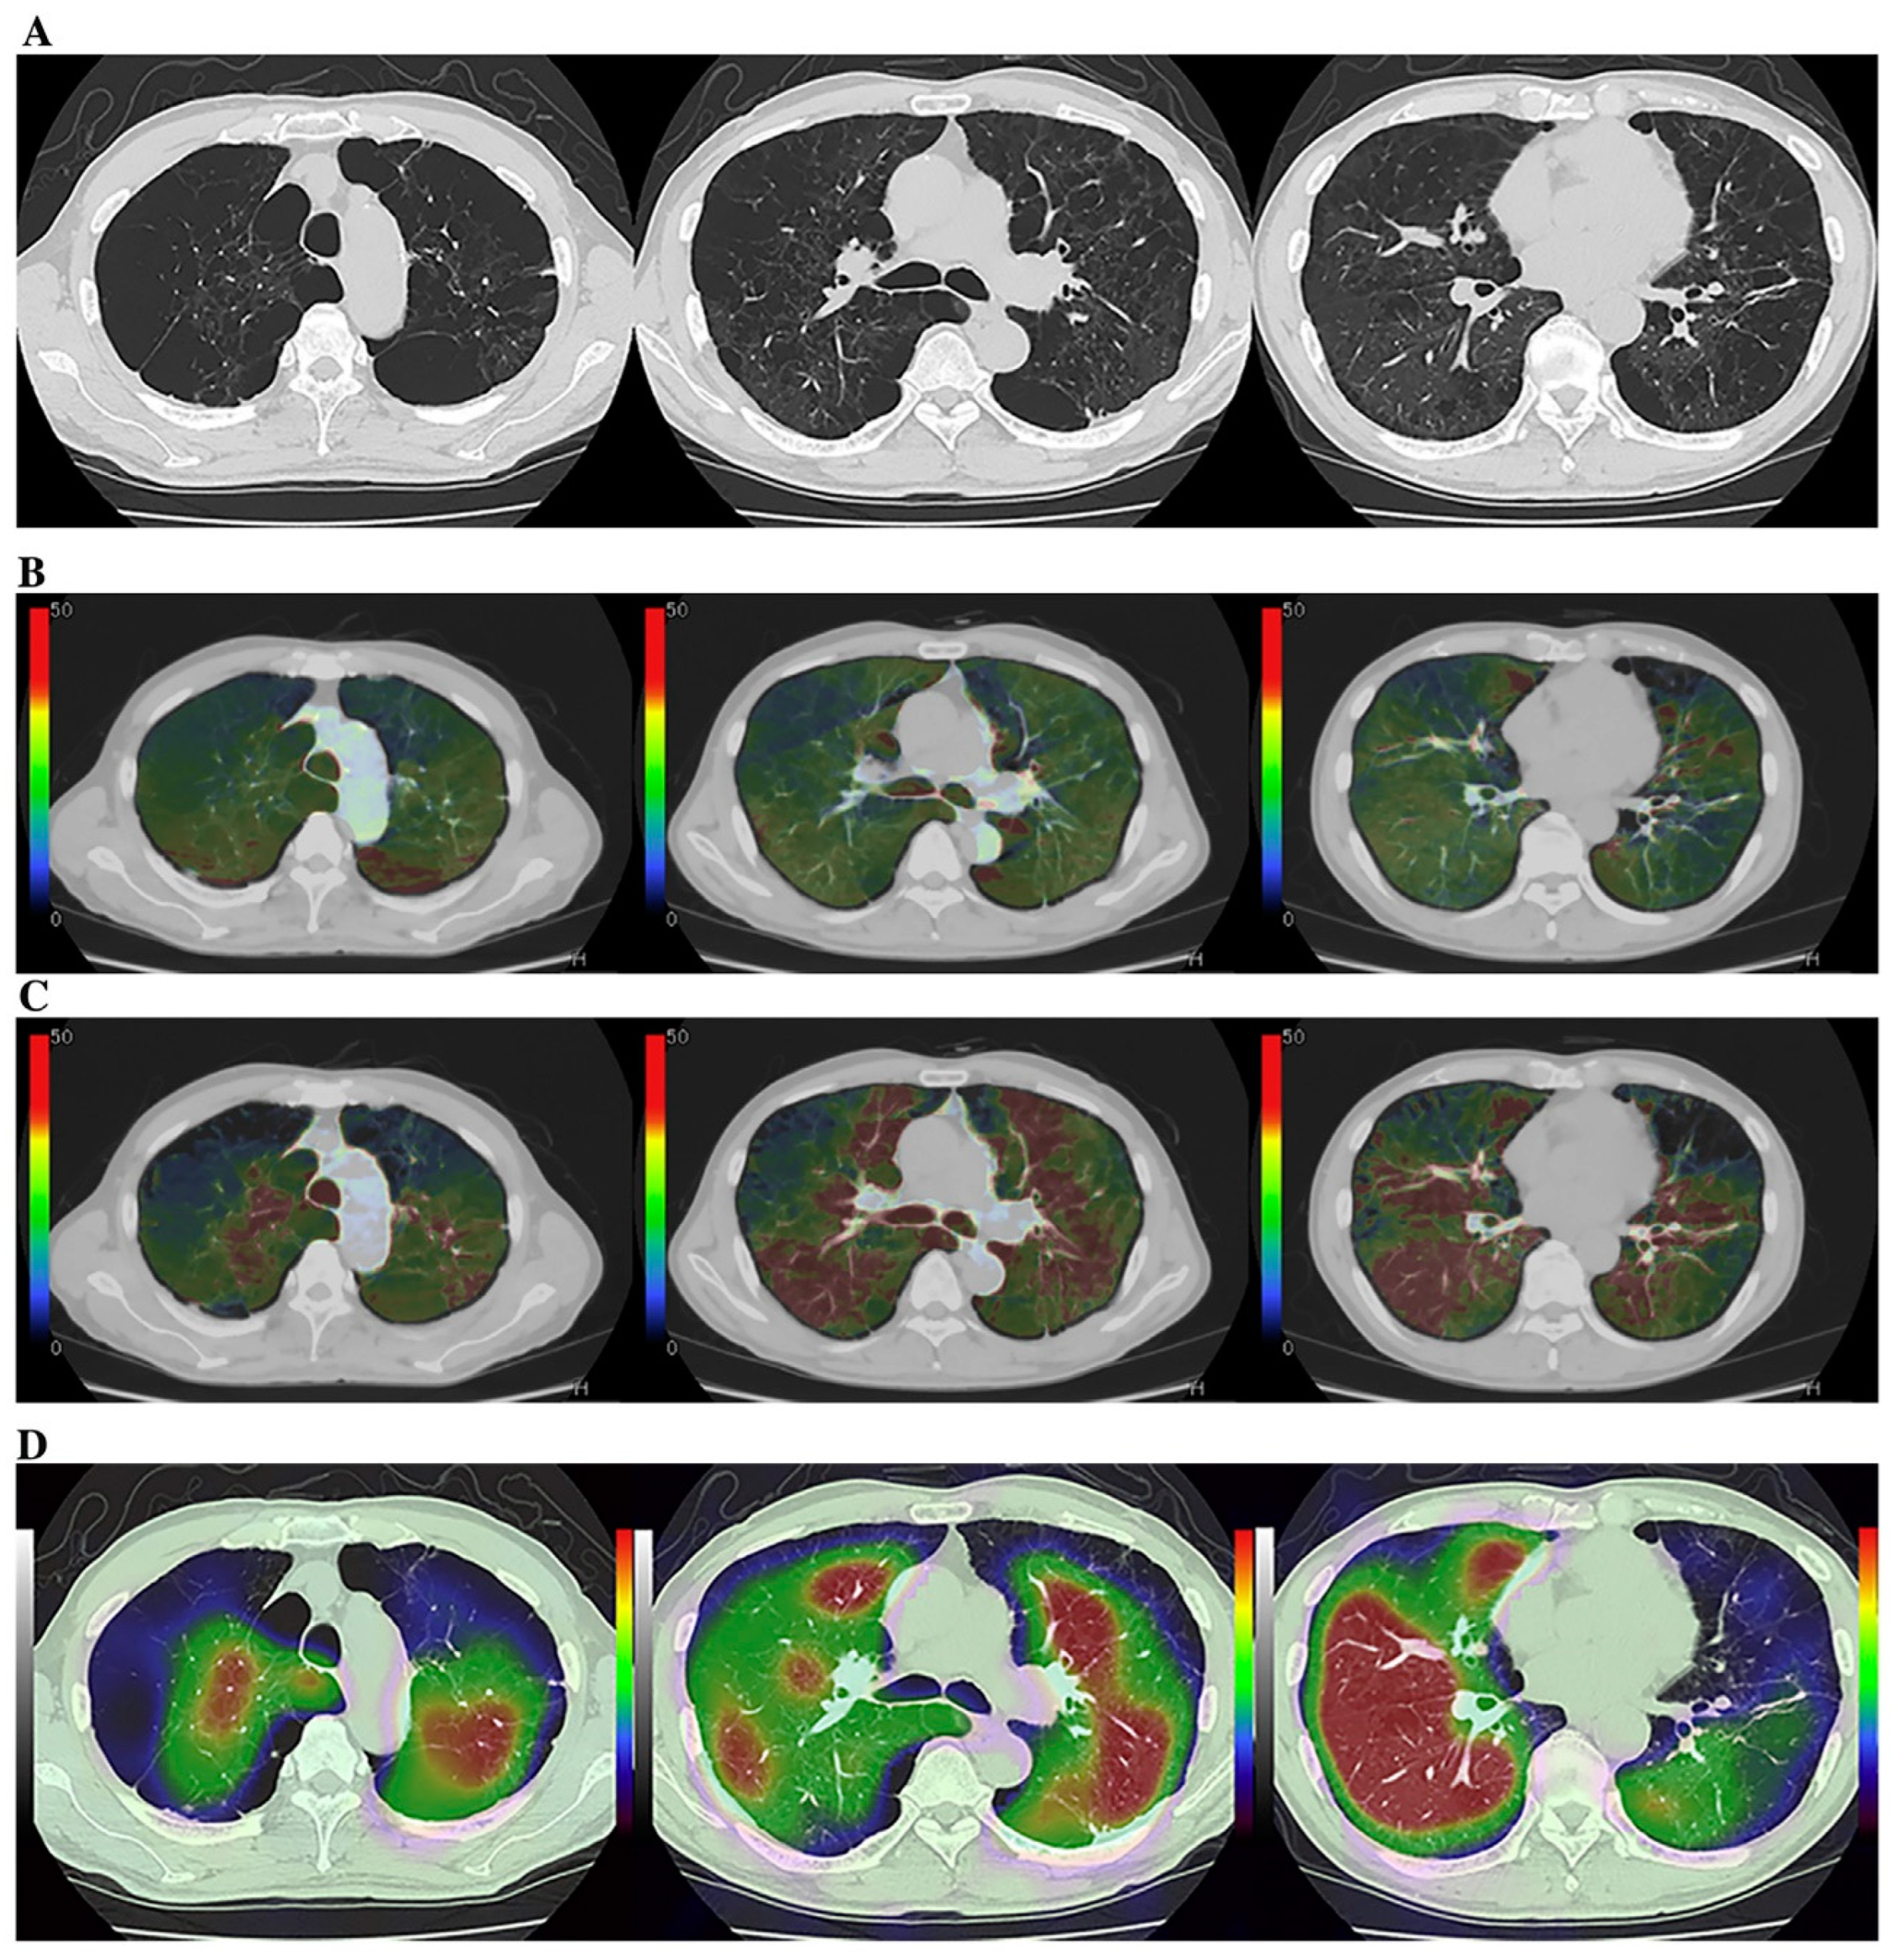

Although the potential of Xe or krypton (Kr) to function as gas contrast media has been known since the 1960s [93,94,95], they were not academically or clinically used for pulmonary functional imaging until 2008. Oxygen-enhanced MRI and hyperpolarized noble gas MRI were reported to be useful for ventilation-based pulmonary functional imaging in the late 1990s [65,66,67,68,69,70]. For this reason, Xe- or Kr-enhanced ventilation CTs have mainly been used for pulmonary functional imaging for in vitro or in vivo studies after the clinical installation of DECT since 2008 [67,68,73,87,96,97,98,99,100,101,102,103,104,105,106,107,108,109,110,111]. Since that time, DECT has been mainly used by dual-source CT systems for patients with COPD or asthma [67,68,73,87,96,97,98,99,100,101,102,103,104,105,106]. However, no studies on the use of ADCT for Xe-enhanced DECT were published until 2023. In contrast to DECT, subtraction ADCT was demonstrated to be as effective as subtraction CT for the visualization of xenon enhancement for in vitro or in vivo studies and for pulmonary functional loss evaluation in comparison with the use of DECT or Kr-81m ventilation SPECT/CT for in vivo studies [107,108,109,110,111]. Moreover, these in vivo studies have demonstrated the potential of Xe-enhanced subtraction ADCT for regional ventilation evaluation or therapeutic effect assessment for smokers, COPD patients, asthmatics, or lung cancer patients [107,108,109,110,111] (Figure 4).

Figure 4.

A 75-year-old male smoker with “Moderate COPD” (58 pack-years, FEV1/FVC%: 55%, %FEV1: 58%) (permission from reference [108]). (A) (L to R: cranial to caudal): Thin-section CT shows a heterogeneously distributed low attenuation area due to pulmonary emphysema. (B) (L to R: cranial to caudal): DECT shows heterogeneous xenon enhancement within the lung and areas of reduced xenon enhancements corresponding well to the distribution of the areas of low attenuation. Total ventilation defect score was 66, and functional lung volume was 65.8%. (C) (L to R: cranial to caudal): Subtraction CT shows heterogeneous xenon enhancement within the lung and areas of reduced xenon enhancement corresponding well to the distribution of the areas of low attenuation. Total ventilation defect score was 88, and functional lung volume was 53.7%. (D) (L to R: cranial to caudal): Co-registered Kr–81m ventilation SPECT/CT shows markedly heterogeneous uptakes within the lung. Regional uptakes correspond well to areas of low attenuation. Total ventilation defect score was 84, and functional lung volume was 55.8%. Regional uptakes of Kr–81m show better correspondence to xenon enhancement on subtraction CT than on DECT.

In addition, inspiratory and expiratory (inspiratory/expiratory) Xe-enhanced subtraction CT with hybrid-type IR has been found to be effective for the assessment of the regional ventilation changes in lung cancer patients due to smoking-related COPD or surgical treatment [110,111]. Although Xe-enhanced subtraction ADCT as well as DECT with dual-source CT are considered to be useful for pulmonary ventilation imaging, cold Xe or Kr has currently not been approved as contrast media for ventilation CT because they were only approved as contrast media for brain CT by the United States Food and Drug Administration, the Japan Pharmaceuticals and Medical Devices Agency, or regulatory authorities in other countries. It is, therefore, vital to obtain, in the near future, the regulatory approval of Xe and Kr as gas contrast media for pulmonary functional imaging, whether Xe-enhanced subtraction ADCT or DECT with dual-source CT are applied.